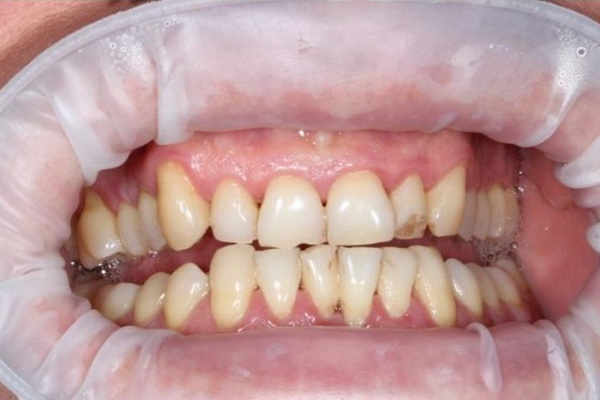

Стан ясен та зубів через 4 місяці після лікування (до та після проведення планової професійної гігієни ротової порожнини).